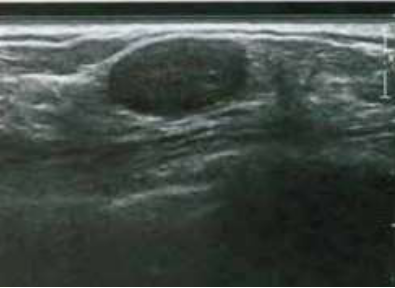

avaliação ultrassonográfica das mamas, devido mamografia com classificação Birads 0. Ao exame observamos um nódulo oval, hipoecóico, sólido, paralelo à pele, contornos definidos, ausência de atenuação posterior, não se observa calcificações e o Doppler é negativo. Qual o possível diagnóstico?